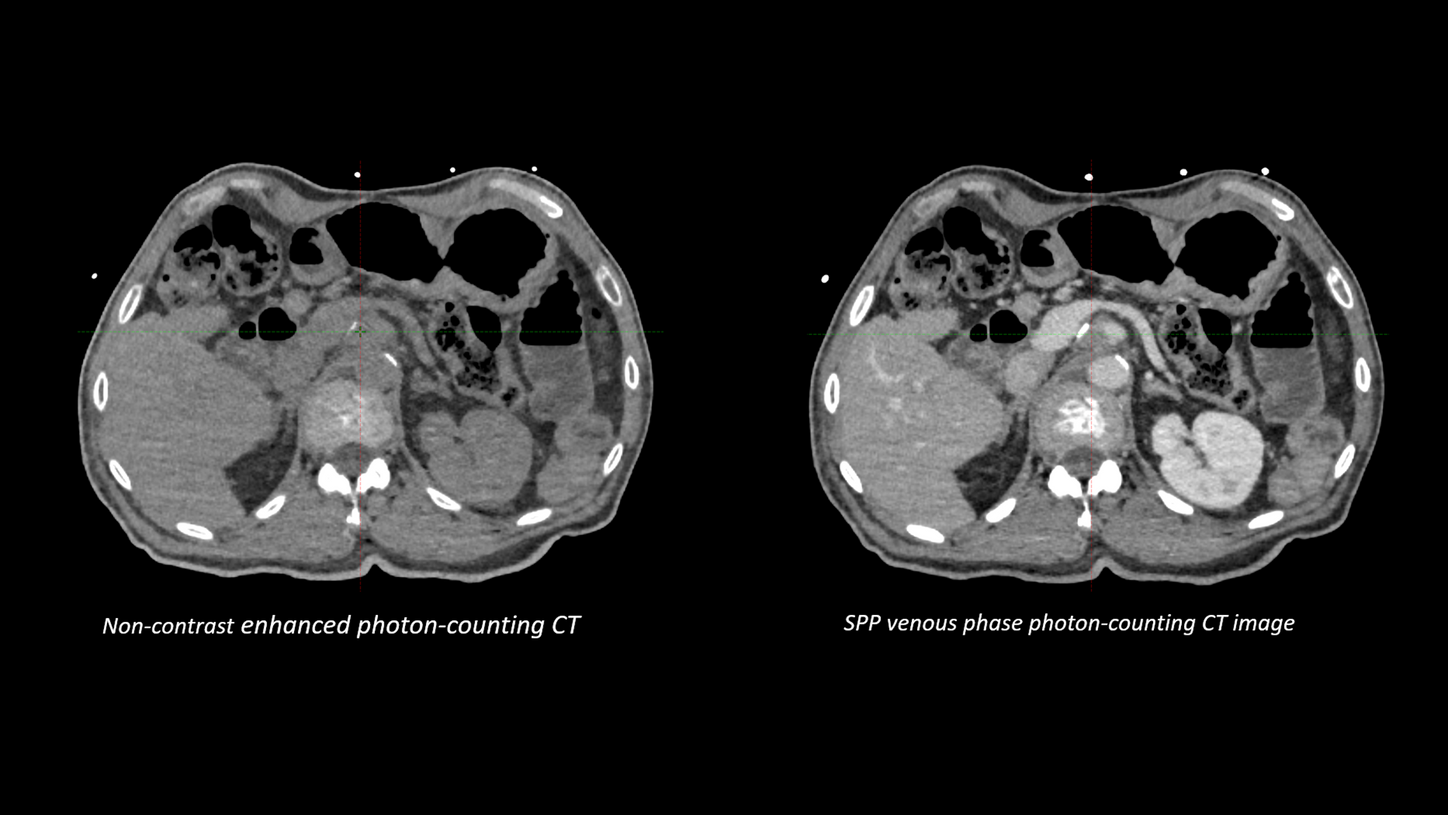

"Compared to previous images, those acquired with our new photon-counting scanner show considerably greater detail. For instance, we can now detect very small liver lesions as small as 4 mm on post-contrast images. The enhanced visibility provided by photon-counting technology enables us to use much narrower margins between the GTV and CTV, allowing for dose escalation鈥攎ight lead to improved patient outcomes." 9